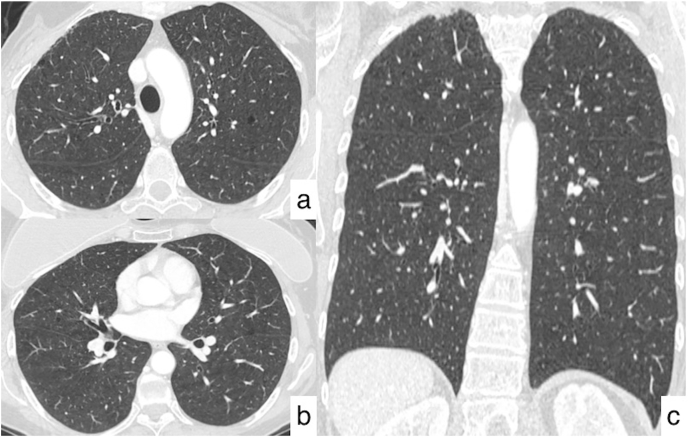

Fig. 4.

Axial (a, b) and coronal (c) HRCT images reveal the presence of multiple bilateral cavitated nodular lesions, having a predominant centrilobular and peribronchial distribution, with no gradient between upper and lower regions.

The following CT examinations have demonstrated the patient's stability over a few years, with no evidence of metastasis (Fig. 3). After five years from the diagnosis of the oncological disease, a new CT follow-up revealed multiple pulmonary nodular lesions, showing predominant centrilobular and peribronchial distribution, with no gradient between upper and lower regions. The majority of these tiny nodules showed cavitated appearance – the biggest lesion reporting a size of 6 mm. In some cases, they were ill-defined with a perilesional area of ground-glass attenuation (Fig. 4). No other pulmonary findings were observed on HRCT images – except for the presence of moderate thickened bronchial walls. According to the patient's clinical history, no signs of lymphatic disease were observed. The bronchocentric distribution of the cavitated nodules suggested the possibility of a small airway disease – due to inflammation and/or infection: however, these CT appearances were not specific, and a differential diagnosis of relapsing disease was considered.